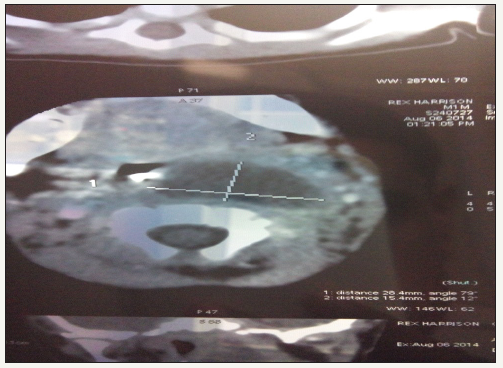

In our study the youngest patient was 45 days old child presented with retropharyngeal abscess and oldest was 70 year old male presented with parotid abscess. 45 days old child presented with stridor, prompt diagnosis of retropharyngeal abscess made with the help of CT scan Figure 2. hild improved after I&D of the abscess.

figure 2: CT scan of 45 days old child showing retropharyngeal abscess.